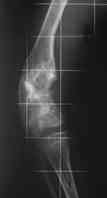

Диагноз: Дисхондроплазия. Варусная деформация дистального метафиза правой бедренной кости; состояние после оперативных вмешательств (1993 и1994 гг.).

Деформация правой нижней конечности с 6 месяцев (стала прогрессировать после года, с момента начала ходьбы). Поставлен диагноз болезнь Олье, варусная деформация, укорочение правой нижней конечности на 4,5 см. 1993 г. - операция остеоклазия на уровне очагов поражения в н/3 правой бедренной кости и в/3 правой большеберцовой кости с одномоментной коррекцией деформации и фиксацией костных фрагментов спицами Киршнера.После начала статической нагрузки (1994 г.) появился рецидив деформации и укорочения. Вторая операция - ЧКО АВФ, аппарат демонтирован через 2недели в связи с развившимся на уровне стержня переломом, после чего находилась в гипсовой повязке до консолидации костных фрагментов. Далеелечилась консервативно в гипсовой повязке. Выраженная деформация и укорочение правой нижней конечности. Относительная длина бедер: справа -34 см, слева - 51 см; анатомическая длина голеней: справа - 29 см, слева - 39 см. Величина варусной деформации на уровне дистального отдела правого бедра составляет - 80 град. Амплитуда движений в коленных суставах (разгибание/сгибание ): справа - 0/0/100 град.; слева - 0/0/30 град. Отмечается боковая и ротационная нестабильность на уровне правого коленного сустава. Амплитуда движений в голеностопных суставах - в норме. Тактика лечения? Заранее благодарю! С уважением,А.В.Владзимирский

Высылаю вам фото подобной больной, у нее тоже первая попытка до меня была безуспешной.

Нужен аппарат Илизарова стабильный с множеством спиц с напайкой, временной фиксацией колена аппаратом на голени. Наверное, проще первый раз начать с бедра, остеотомию выполнить прямо на уровне перехода очага в дистальный метафиз бедра. Дистракционный остеогенез вызовет перестройку хрящевой ткани в костную. Понадобится еще пара этапов.